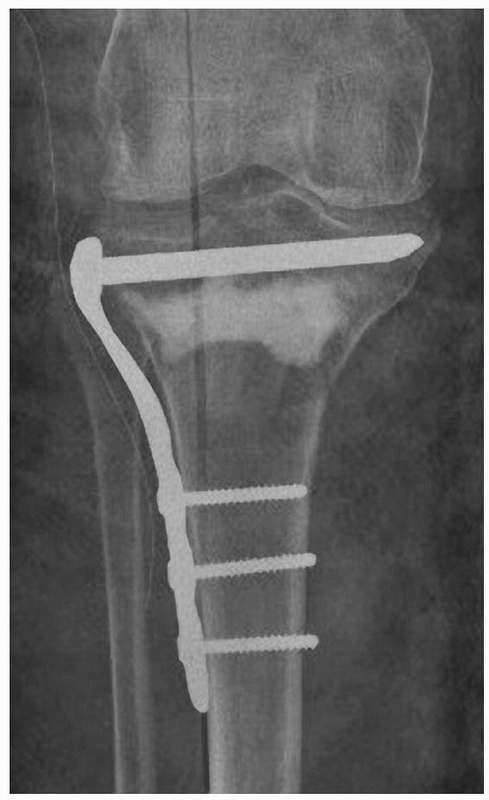

increases the strength of the fixation. Threaded screw holes in the

plates create angular stability between the screws and the plates. For

example, the locking compression plates (LCP) provide 3 times greater

stability than a standard lateral condylar buttress plate and about 2.5

times greater stability than a 95-degree condylar plate in axial

loading.157 This strength is increased if the screws are fixed at multiple angles.266 The use of these multiple screws in fixed angle devices is particularly useful in the metaphyseal region (Fig. 18-8).